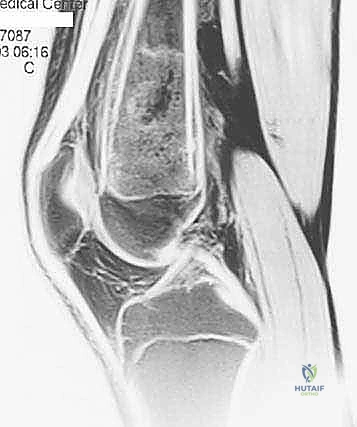

- الرنين المغناطيسي (MRI): هو المعيار الذهبي (Gold Standard) لتقييم الأورام. يوضح بدقة امتداد الورم في النخاع العظمي والأنسجة الرخوة، وعلاقته بالأعصاب والأوعية الدموية.

يعتمد الأستاذ الدكتور محمد هطيف على دراسة هذه الصور الإشعاعية شخصياً قبل تحديد مسار إبرة الخزعة، لضمان عدم تلويث الحجرات العضلية السليمة (Compartments).

الحالة الأولى: إنقاذ ركبة رياضي شاب

شاب يبلغ من العمر 19 عاماً عانى من ألم مستمر في الركبة وتورم لم يستجب للمسكنات. بعد الفحص السريري الدقيق وإجراء الرنين المغناطيسي، اشتبه الأستاذ الدكتور محمد هطيف بوجود ورم. تم إجراء خزعة إبرة أساسية دقيقة جداً. أظهرت النتائج وجود "ساركوما عظمية" في مراحلها الأولى. بفضل الخزعة الدقيقة التي لم تلوث الأنسجة المحيطة، تمكن الدكتور هطيف لاحقاً من استئصال الورم بالكامل وتركيب مفصل صناعي خاص بالأورام، مما أنقذ ساق الشاب من البتر ومكنه من العودة للمشي بشكل طبيعي.